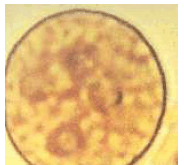

A imagem abaixo mostra um cisto de Entamoeba histolytica corado com lugol diluído.

A visualização de cistos nas fezes pode ser melhorada com a adição de uma gota da solução de iodo 1 g, iodeto de potássio 2 g e água destilada 100 mL.